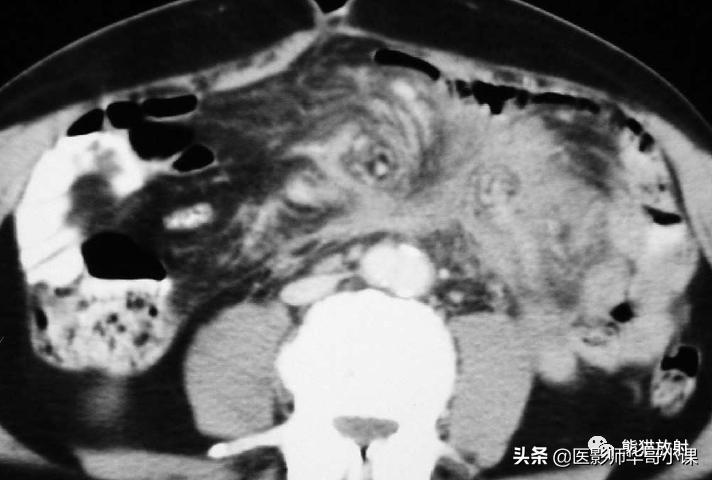

回缩性肠系膜炎CT表现 为浸润性软组织密度肿块,周围可见放射状条索影(图),这些特点可能与纤维瘤病或类癌相似。 硬化性肠系膜炎 在T1WI和T2WI图像上均呈低信号,有助于疾病的鉴别。肿块中央坏死区可见钙化(图)。该病有一定的自限性,通常预后较好。

纤维性肠系膜炎。不明原因发热患者,增强CT显示边缘不规则纤维脂肪样肠系膜肿块包绕肠系膜血管。从肿块到相邻的肠系膜脂肪可见放射状软组织条索影。

纤维性肠系膜炎。CT表现增强CT显示大而边界模糊、广泛钙化的肠系膜软组织肿块。注意邻近的肠襻回缩及增厚。